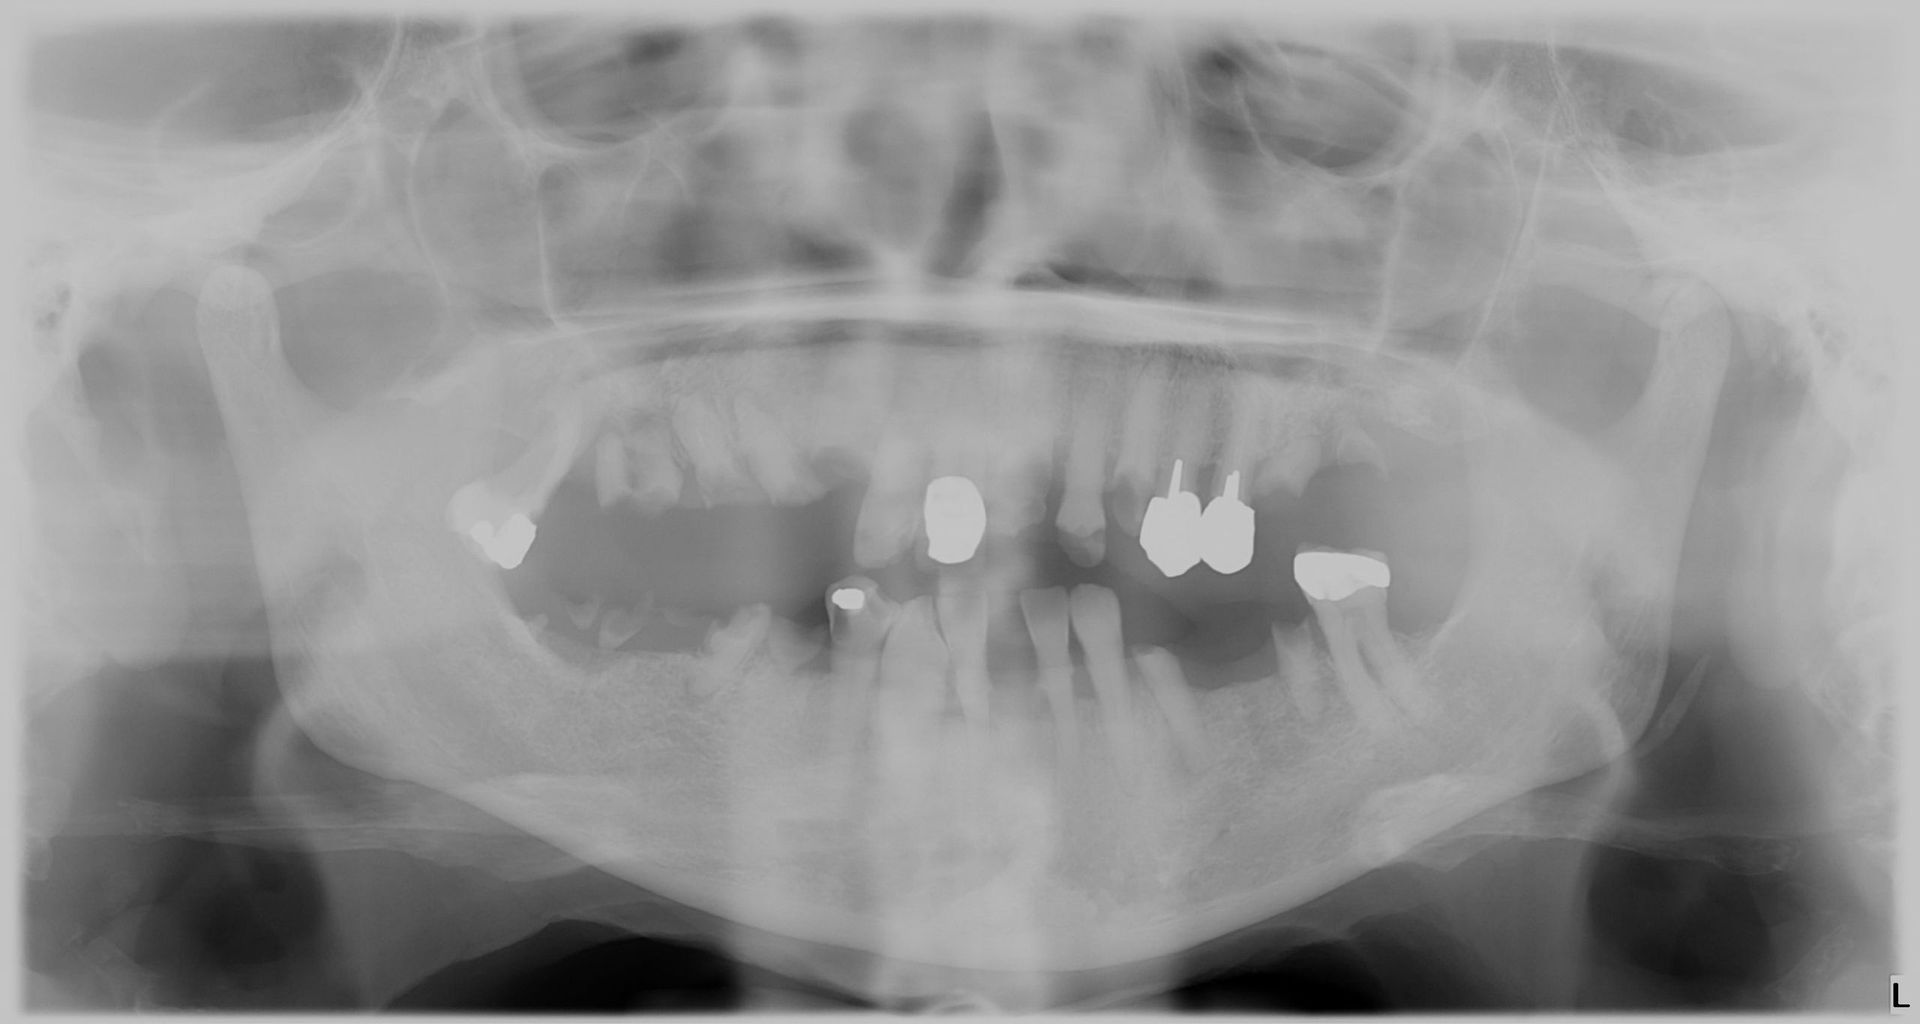

Avant et après parodontite